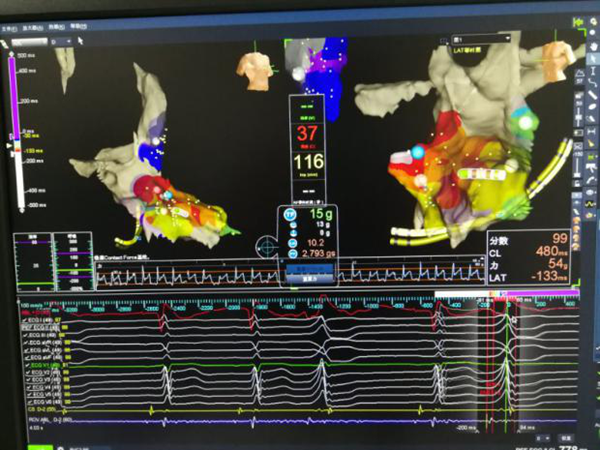

三维显示主动脉瓣下消融靶点

患者进入手术室麻醉后,室早消失,薛荣亮主任和李伟主任对麻醉药物精确滴定,既保证有稳定的室早出现,又保证患者的麻醉效果。超声室金鑫医师迅速实施食道超声插管。心内科郑强荪主任、王洪涛医师、郝广华医师和苏丹医师随即实施手术。首先穿刺股动脉,将消融导管逆行送入主动脉窦部位,在主动脉金属瓣上谨慎操作,行激动标测,未标记到室早最早激动点。考虑患者存在主动脉瓣金属瓣,消融导管不宜直接跨瓣膜操作,遂穿刺股静脉,在食道超声指导下行房间隔穿刺,将可调弯鞘管和消融导管依次送入左房、左室,以非同平面双弯角度最终把消融电极成功送入主动脉瓣下,标记到室早最早激动点。随着放电消融的“滴滴声”,10秒后,室早即刻终止。逐步增加功率,巩固消融后,室早未再出现,大家如释重负。术后持续心电监护显示,室早一个都没有出现,彻底解决了困扰患者多年的心悸问题。

主动脉瓣上激动标测

主动脉瓣下激动标测和射频消融